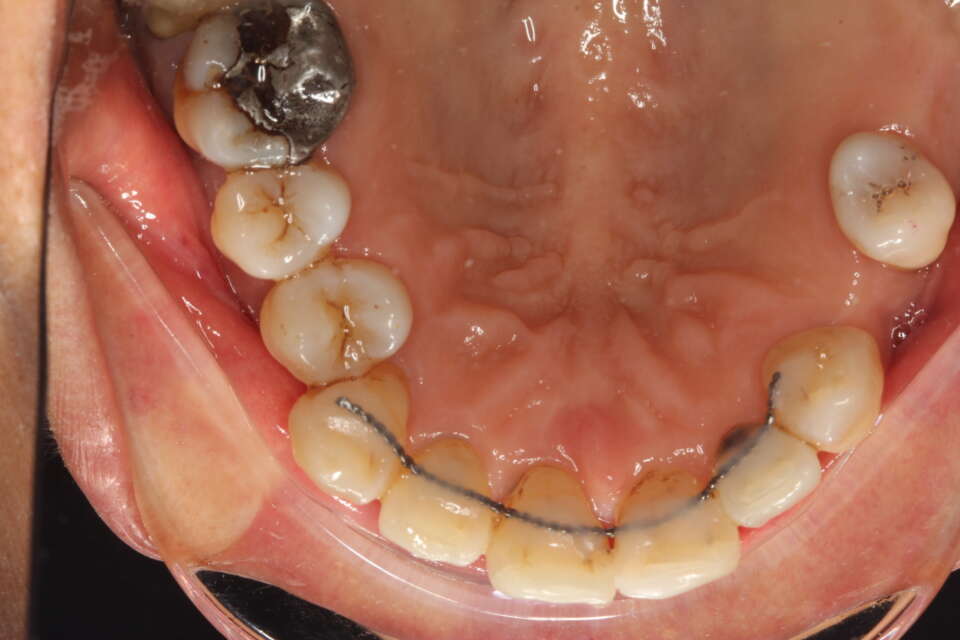

Lingual brace in situ

IMG 6771

From this view, you can see the extent of the crowding